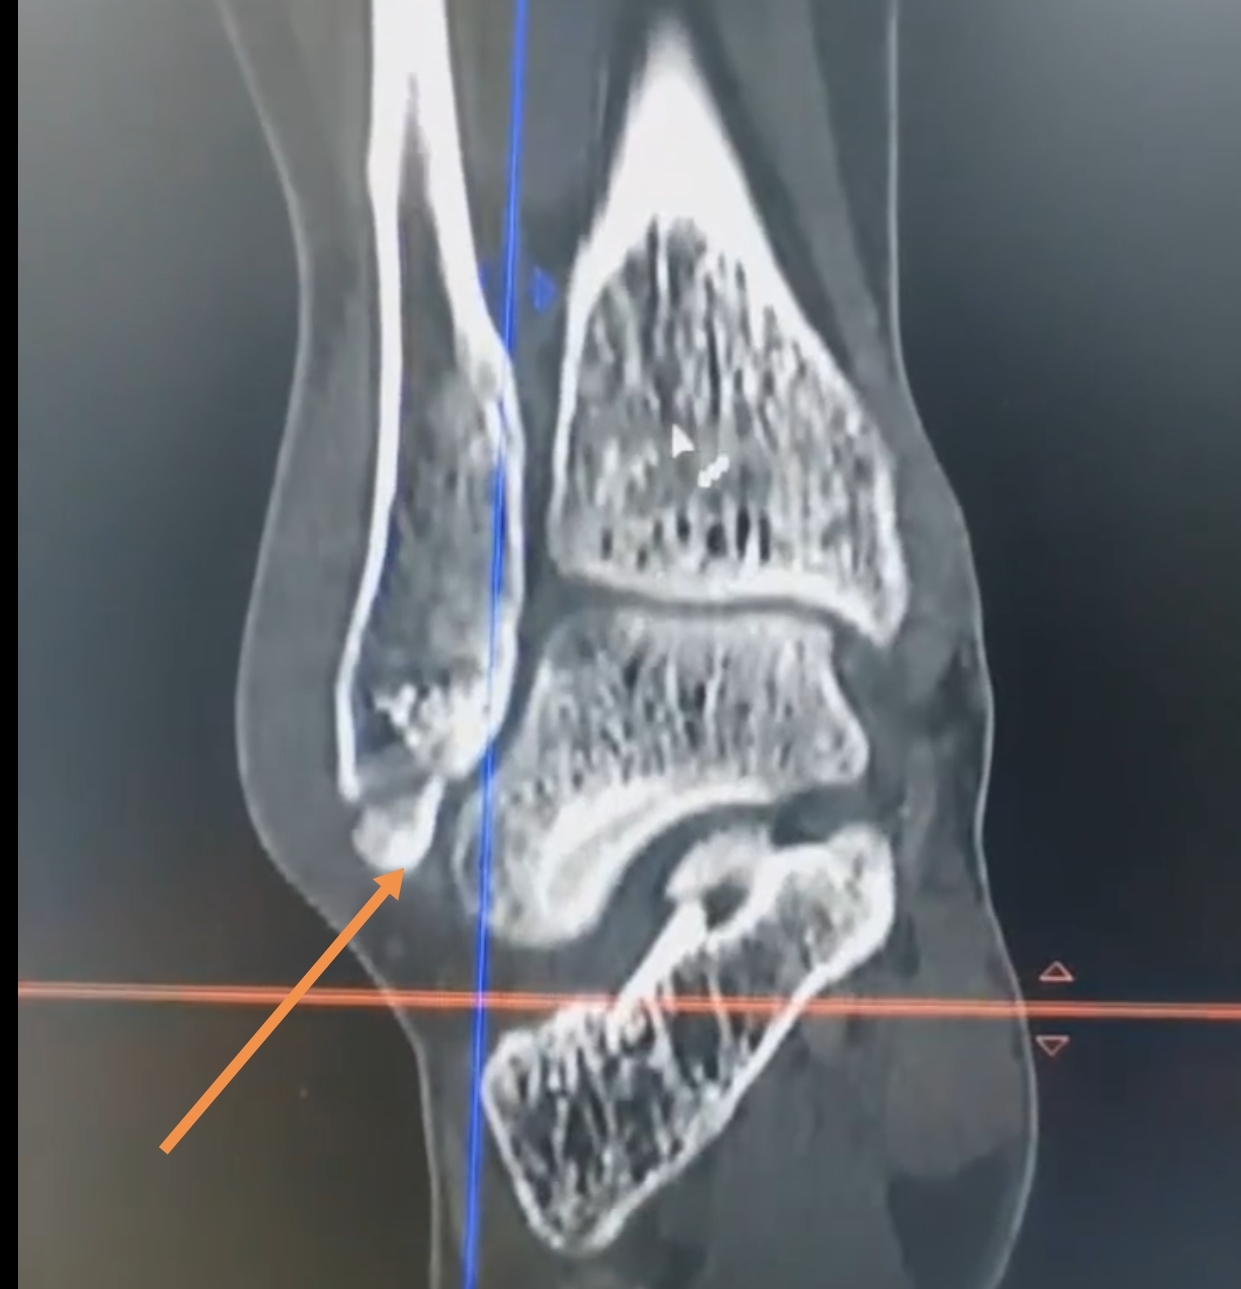

踝關(guān)節(jié)扭傷是臨床中最常見的足踝部外傷,除了常見外側(cè)韌帶復(fù)合體損傷或者各類Lauge—hensen分型的踝關(guān)節(jié)骨折外,其中有一類比較特殊腓骨遠(yuǎn)端的撕脫骨折。如圖1這類患者表現(xiàn)為外踝腫脹疼痛伴活動(dòng)受限。在CT上表現(xiàn)為一個(gè)輕度的移位或者沒有移位?;颊呔驮\時(shí)往往收到兩種截然相反的意見,一個(gè)是必須接受切開復(fù)位內(nèi)固定手術(shù),一個(gè)是完全通過石膏或支具固定一段時(shí)間就可以痊愈。從原則來說,兩種方法都沒本質(zhì)錯(cuò)誤。這一類腓骨撕脫骨折,實(shí)質(zhì)上是一類韌帶止點(diǎn)撕脫骨折,接受保守治療,一般骨折愈合完全沒問題,而且由于很少累及踝關(guān)節(jié)軟骨面,所以即便有一些移位也不會(huì)導(dǎo)致遠(yuǎn)期創(chuàng)傷性骨關(guān)節(jié)炎發(fā)生。那么為什么有的醫(yī)生提倡手術(shù)呢,如圖2手術(shù)的好處在于,術(shù)后可以早期功能鍛煉,避免了長期固定帶來的廢用性肌肉萎縮,關(guān)節(jié)僵硬。所以腓骨遠(yuǎn)端撕脫骨折是否手術(shù),更需要結(jié)合患者的全身情況和意愿,選擇適合的治療方案。